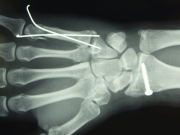

图源网络

在古籍中我们能了解到古代对骨折的病理的记载,在实践当中,各朝代也有许多具体的治疗方式。据医书记载,汉代以前,人们对骨折大多采取包扎固定的方法。秦汉之间,包扎材料多半用麻和丝织品。

魏晋时期,骨折包扎方式有进一步的发展。医学家葛洪在《肘后救卒方》一书里,首次记载了用竹片固定骨折的疗法,开创了夹板固定骨折的先例,葛洪最先使用的是竹片。古代书籍都为竹简,因此竹片随处可取。

唐代的蔺道人用杉木皮固定骨折。蔺道人的《理伤续断秘方》里记载:杉木皮用水浸泡,软了以后,削成手指大的薄片,每片之间,留一条小缝,用细绳子上、中、下三道捆扎好。哪里受伤,用药后就牢牢地捆缚在那里。关节处还是食用绢布,以便日常轻微弯曲,有利于骨折的恢复。